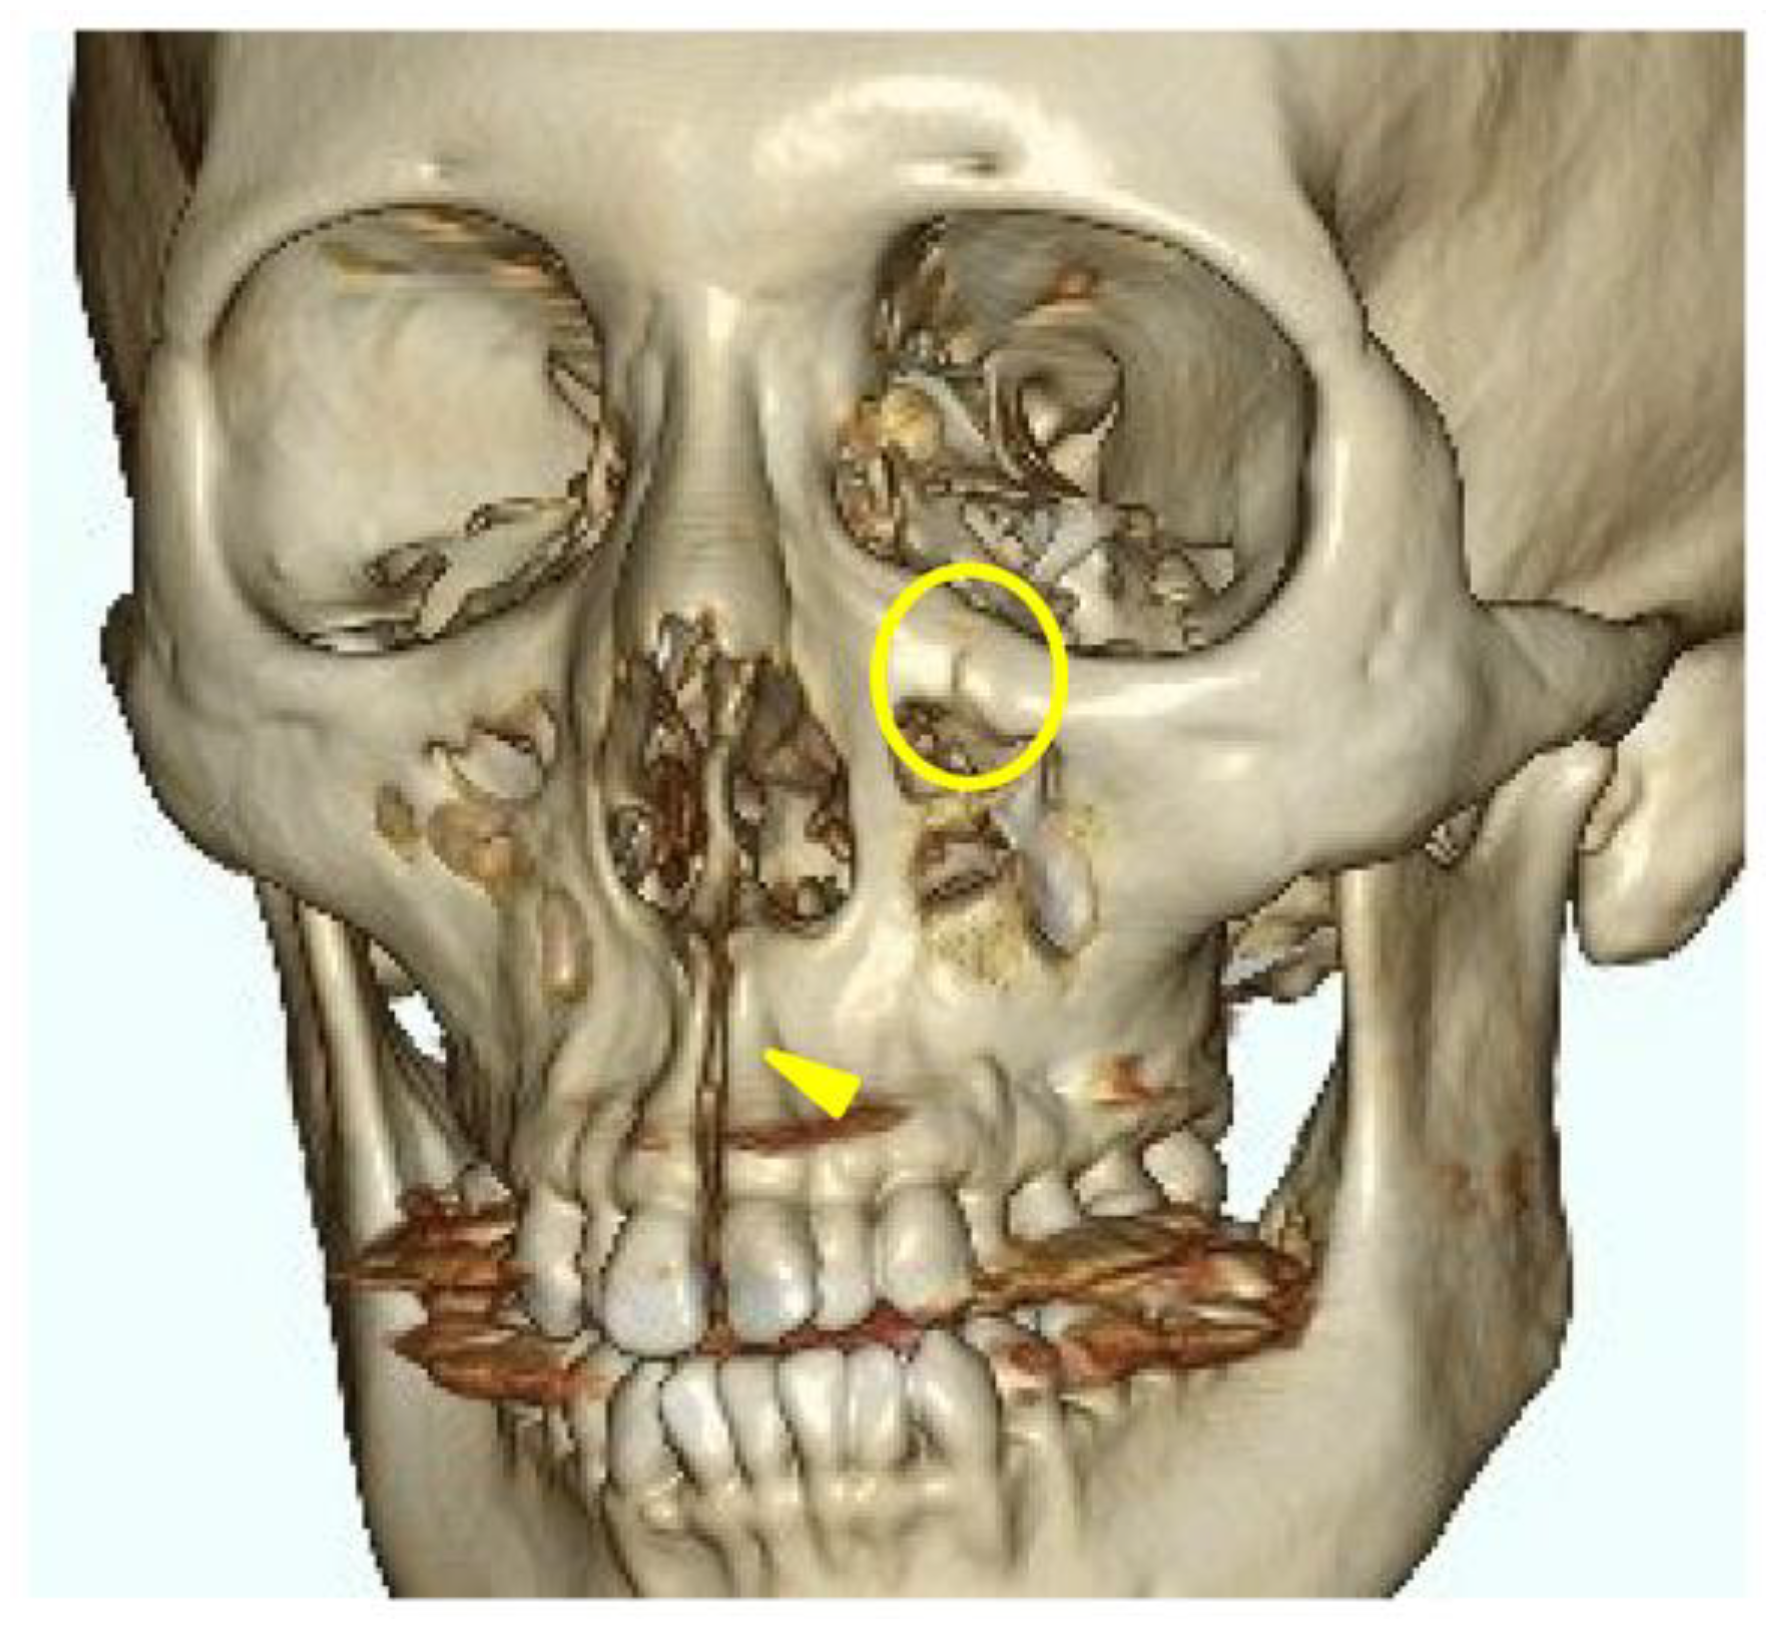

A head CT was performed on the same day. The axial slices revealed a 4-mm-wide separation of the midpalatal suture (Figure 3). A fracture of the left maxilla was also observed. The line of this fracture extended from the orbital floor and the anterior surface of the maxilla (Figure 4), starting at the medial edge of the orbital rim, passing through the entire wall of the infraorbital foramen (Figure 5a, b), and reaching the maxilla’s alveolar process. Three-dimensional CT reconstruction revealed that the rapid expansion of the maxilla had been resisted by the surrounding bones, particularly the zygomatic bones, leading to the observed fracture.

A fracture line extending from the infraorbital rim to the infraorbital foramen (Circle mark) and a separation of the midpalatal suture (Yellow triangle marks) are observed.

Figure 4. Three-dimensional computed tomography image of facial bones.

In this case, the fracture was concentrated around the zygomatico-maxillary suture for reasons that are unclear; however, there are studies investigating the correlation between the ossification state of facial bone sutures and the effects of rapid maxillary expansion (RME) devices [7]. Provatidis et al. [7] analyzed the effects of RME on the craniofacial complex using finite element modeling, a computer simulation method, by applying RME to a dry human skull. Their analysis revealed that while the lacrimomaxillary, frontomaxillary, and nasomaxillary sutures had little influence on RME outcomes, the zygomatico-maxillary suture was significantly affected. These findings may have something to do with the underlying mechanisms of the fractures observed in this case. Furthermore, in trauma-induced zygomatic fractures, it is well-known that fracture lines frequently pass through the infraorbital foramen and that sensory disturbances of the second branch of the trigeminal nerve are typical symptoms of such fractures [8,9]. Therefore, the infraorbital foramen is inherently a site prone to fractures caused by external forces, and a MARPE-induced fracture is highly likely to involve this area.